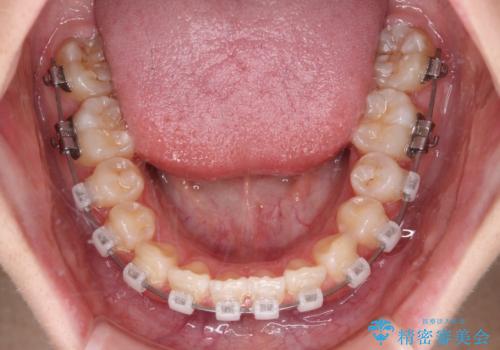

- 矯正装置

- クリアブラケット

- 治療期間

- 11ヶ月

ワイヤー矯正でもマウスピース矯正でも対応可能でしたが、マウスピース矯正の自己管理が面倒であること、上顎前歯の捻転が著しいことから、ワイヤー矯正での治療を希望されました。

インビザライン治療が継続できない性別と年齢が世界的に調査されているそうですが、ほとんどの国で女子高生が最も多いとのことです。